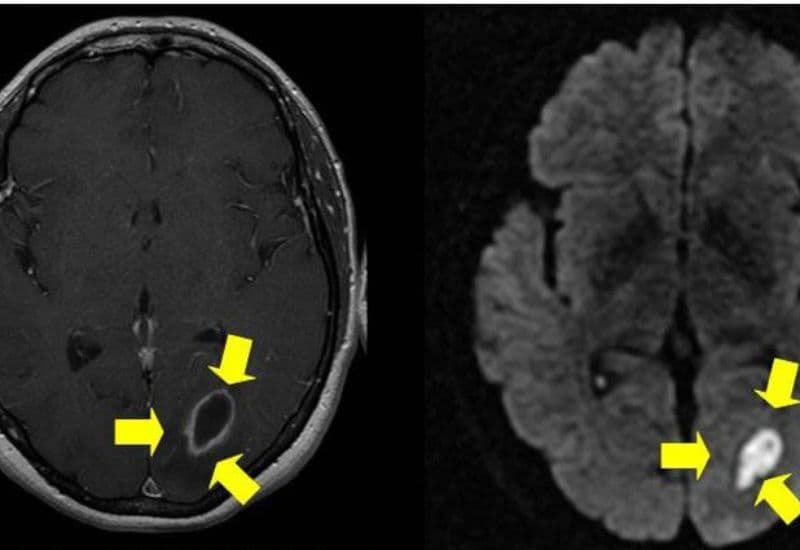

Đây là một biến chứng hiếm gặp nhưng vô cùng nghiêm trọng. Khi vi khuẩn từ ổ áp xe tai lan vào não, chúng có thể tạo ra các ổ áp xe trong mô não. Điều này gây áp lực lên não, dẫn đến các triệu chứng như đau đầu dữ dội, buồn nôn, nôn mửa, co giật và thậm chí là hôn mê. Áp xe nội sọ là tình trạng cấp cứu đòi hỏi phải được điều trị ngay lập tức, thường là qua phẫu thuật để loại bỏ ổ mủ.

Áp xe tai biến chứng nặng có thể gây áp xe nội sọ, một biến chứng rất nghiêm trọng đe dọa đến sức khỏe của người bệnh. (ảnh minh họa)